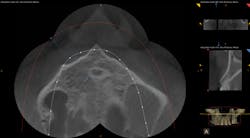

Upon taking the scan, we found a thumb-sized lesion in the No. 14 region and large cysts on Nos. 13 and 15. It turned out that when the patient was practicing tae kwon do in the late 1990s (he was a second-degree black belt), he got kicked in the face, which caused the bone under the teeth to basically die. He had all of these issues as a result, and they kept getting diagnosed as other conditions. His first root canal was in 1999, and it took a 3-D scan in 2015 to finally get to the source of the problem.